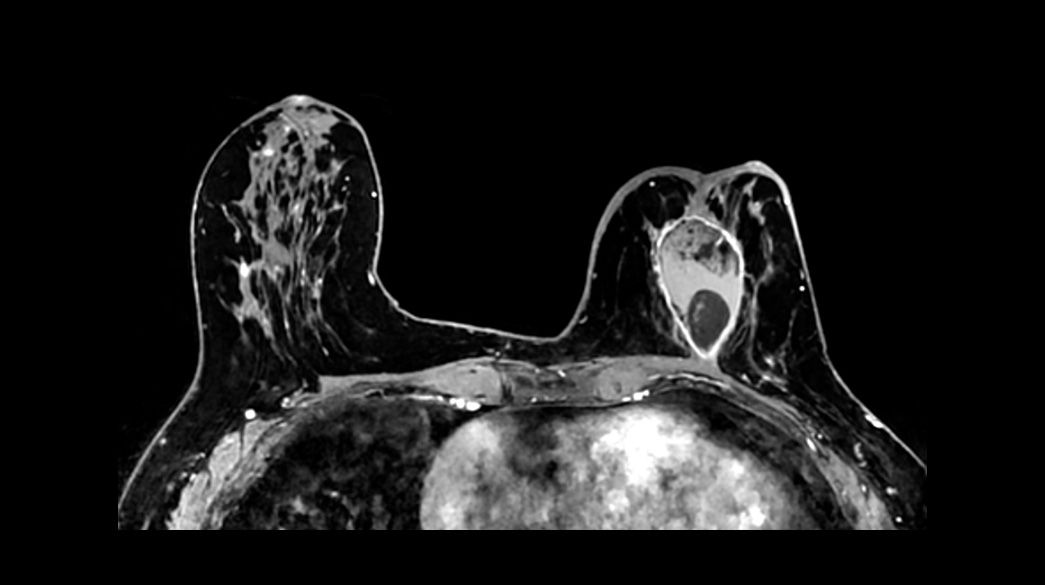

Precision and personalization

Vibrant-and-VibrantFlex1040-x-585

Read case study ico-caret-right

MR image reconstruction with AIR™ Recon DL

AIR™ Recon DL has revolutionized MR imaging with deep-learning based image reconstruction increased image quality, reduced scan time and improved SNR.